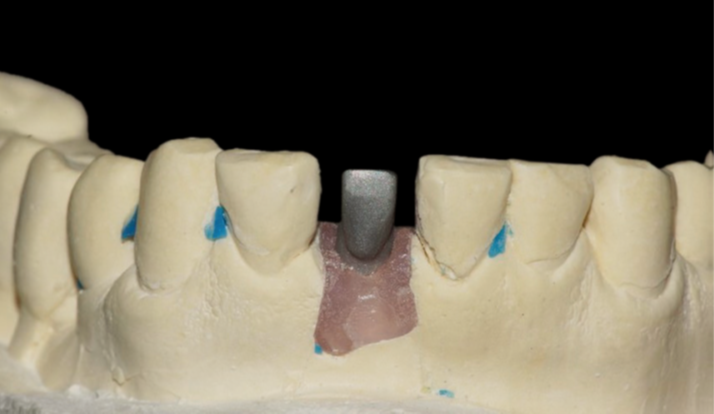

Assim, um coping de titânio (Implacil De Bortoli) foi utilizado para a confecção da restauração provisória instalada em seguida, permanecendo no local por 15 dias para formação do novo perfil de emergência no elemento 41 (Figura 6). Então, o provisório foi removido, o novo perfil de emergência foi constatado e o transferente de moldagem correspondente ao tamanho do pilar foi posicionado para a execução do procedimento (Figuras 7 e 8). A moldagem foi realizada com silicone de condensação (Optosil e Xantopren, Kulzer) e, após a polimerização do material, o molde foi retirado arrastando consigo o transferente de moldagem (Figura 9). O análogo foi inserido no transferente e o molde foi vazado com gesso especial tipo IV (Durastone), sendo realizada a confecção do coping metálico no laboratório (Figuras 10 e 11).

Após sete dias da moldagem, o coping foi provado em boca para verificar a boa adaptação e fixação. A seleção da cor foi realizada com o uso da escala Vita cor A3, e o provisório voltou a ser instalado (Figura 12).